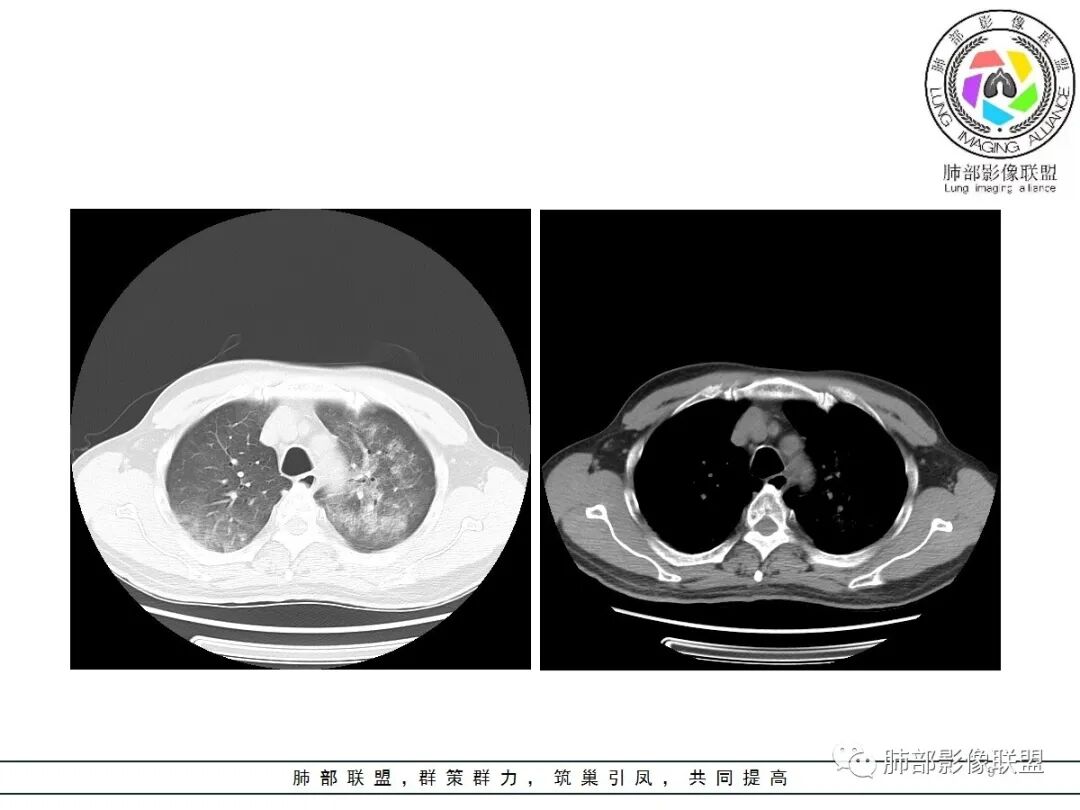

影像:双肺对称性中内带为主分布磨玻璃影,实变不明显。无胸水及小叶间隔增厚。

病史中D2聚体明显升高,影像:双肺对称性中内带为主分布磨玻璃影,有坠积感,实变不明显,胸膜下回避。无胸水及小叶间隔增厚;肺水肿?感染?建议CTPA检查除外肺栓。

老年男性,咳嗽发热38度1天,crp、血象增高,pct不高,血气尚可,饲鹦鹉。双肺弥漫中心性多发磨玻璃密度影,以肺门区为中心性GGO伴细网格,无小叶间隔增厚,考虑非典,鹦鹉热?鉴别DAH

CT示双肺中内带多发斑片状磨玻璃影,沿支气管血管束分布,边界模糊,部分支气管壁增厚。定位气道来源的病变,考虑非典型病原体感染,鹦鹉热可能。

男,65,咳嗽、发热1天,黄粘痰,痰中带血。饲养鹦鹉,新冠疫苗第二针后,本地有新冠病例。血像高。胸部CT:双肺中内带多发斑片样磨玻璃影,边缘不清,沿支气管血管束分布,左肺重,细网络,小叶内间隔增厚,支气管充气征。诊断:肺门为中心两侧大概对称GGO,首先考虑DAH(血管炎)?不典型病原体感染,鹦鹉热、病毒待排。鉴别肺水肿、PCP等。